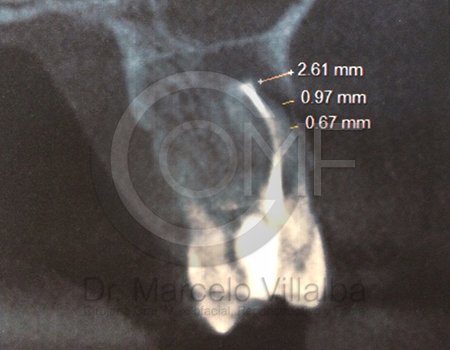

CIRUGÍA ORTOGNÁTICA EN DEFORMIDADES O ASIMETRÍAS FACIALES

Es una cirugía en la que se busca mover el maxilar, mandibular y mentón o sólo una de estas estructuras para alcanzar una combinación médico-odontológica, así llegar al fin estético y funcional del aparato estomatognático y facial.